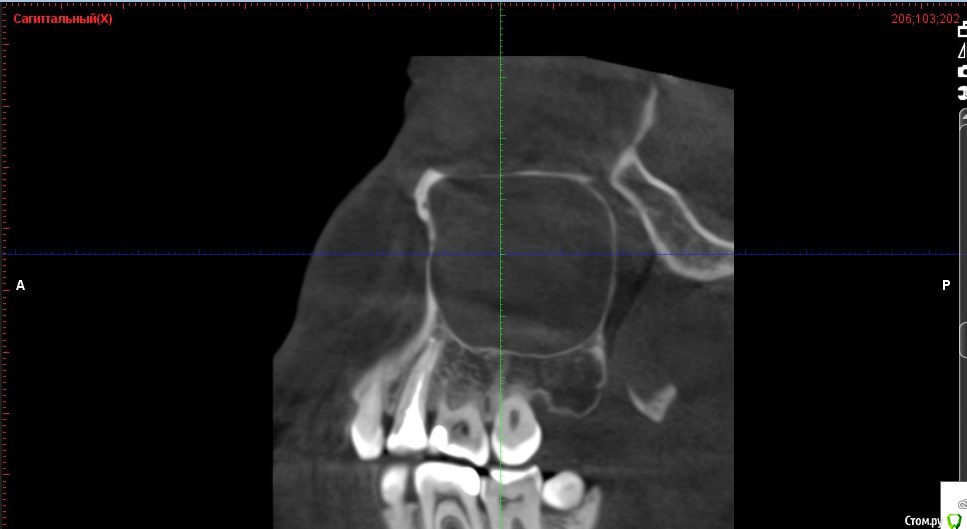

Verasss Опубликовано 8 октября, 2016 Автор Поделиться Опубликовано 8 октября, 2016 КТ от 08.09. Извините, что в таком виде, надо менять ОЗУ. Ссылка на комментарий

Verasss Опубликовано 28 октября, 2016 Автор Поделиться Опубликовано 28 октября, 2016 Добрый вечер! Ещё раз попытаюсь прикрепить скриншоты КТ от сентября. Если качество совсем не устраивает, подскажите, пожалуйста, какие сделать снимки?К сожалению, программа не позволяет вывести снимки на полный экран и заскриншотить в более хорошем качестве. Ссылка на комментарий

Verasss Опубликовано 28 октября, 2016 Автор Поделиться Опубликовано 28 октября, 2016 еще снимки Ссылка на комментарий

Verasss Опубликовано 28 октября, 2016 Автор Поделиться Опубликовано 28 октября, 2016 и еще Ссылка на комментарий

DmitrySH Опубликовано 8 октября, 2016 Поделиться Опубликовано 8 октября, 2016 В таком виде КТ малоинформативно. Но гайморита нет. Ссылка на комментарий